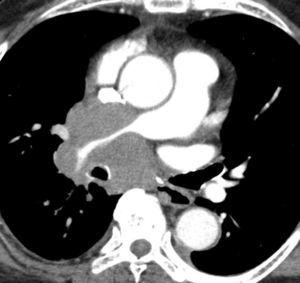

Valoración del tumor

El estadio tumoral (T) se basa en el tamaño, localización y relación con las estructuras adyacentes valorado mediante TC. Los tumores T1 son aquellos de 3 cm o menores en su diámetro mayor, rodeados de pulmón y que no invaden la pleura visceral ni los bronquios principales, mientras que los T2 son lesiones mayores de 3 cm, o aquellas que invaden la pleura visceral o al bronquio principal a más de 2 cm de la carina o que condicionan atelectasia o neumonitis obstructiva que no afecte a todo el pulmón. La diferenciación entre ambos estadios tumorales suele ser sencilla mediante TC, salvo la afectación de la pleura visceral, aunque esta no tiene un impacto importante en el manejo clínico. El tumor T3 viene determinado por la infiltración de estructuras vecinas potencialmente resecables, como la pared torácica, diafragma, pleura mediastínica, pericardio parietal o si el tumor está situado a menos de 2 cm de la carina (fig. 1). Los tumores T4 son aquellos que no pueden ser resecados porque engloban a estructuras vitales, invaden el corazón, grandes vasos, esófago o cuerpos vertebrales (fig. 2) o en los que existe un nódulo o nódulos en el mismo lóbulo del tumor. Además de definir la T, es importante reflejar las particularidades de la infiltración de estructuras en vecindad que puedan modificar la actitud terapéutica. Por ejemplo, cambiará la estrategia quirúrgica según el tipo de bronquio afecto o la estructura mediastínica infiltrada, si es sólo la grasa, o un vaso; cuando existe neumonitis o atelectasia secundaria a un tumor central, la planificación del campo de radioterapia dependerá del límite entre la masa y la repercusión pulmonar.

Fig. 2.--T4. (A) Corte axial de tomografía computarizada (TC) torácica con contraste. Tumor hiliar derecho que infiltra la arteria pulmonar derecha, la vena cava superior y engloba al bronquio intermediario. (B) Reconstrucción coronal oblicua, longitudinal al eje de la arteria pulmonar derecha, que muestra cómo engloba el tumor a la rama del truncus superior (flecha blanca) e inferior (flecha negra).